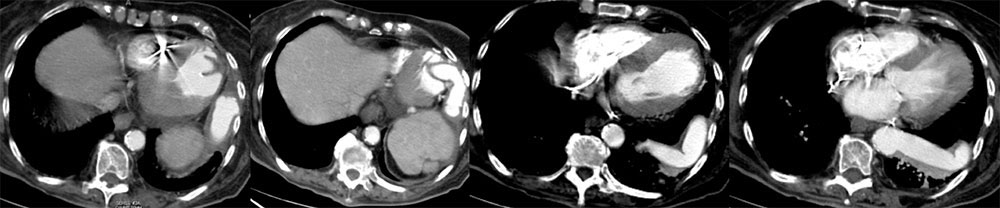

Case 9  49 year old woman status post cytoreductive surgery 2 weeks prior. IV contrast enhanced CT shows:

Case 9  49 year old woman status post cytoreductive surgery 2 weeks prior. IV contrast enhanced CT shows:

Retained Metal Malleable Retractor